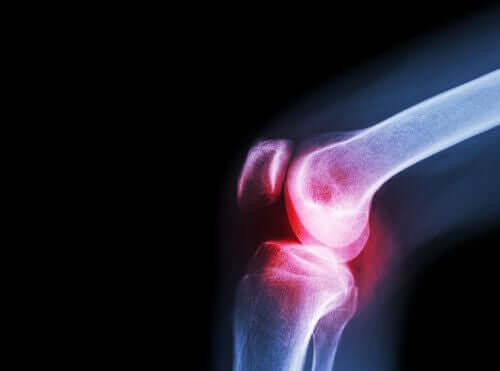

Charakteristisch für Lupus erythematodes sind außerdem Gelenkschmerzen. Diese entstehen durch Arthritis, die durch diese Autoimmunkrankheit vom Körper ausgelöst wird. Die Entwicklung der Arthritis verläuft meist abwechselnd in akuten Schüben und schmerzfreien Phasen.